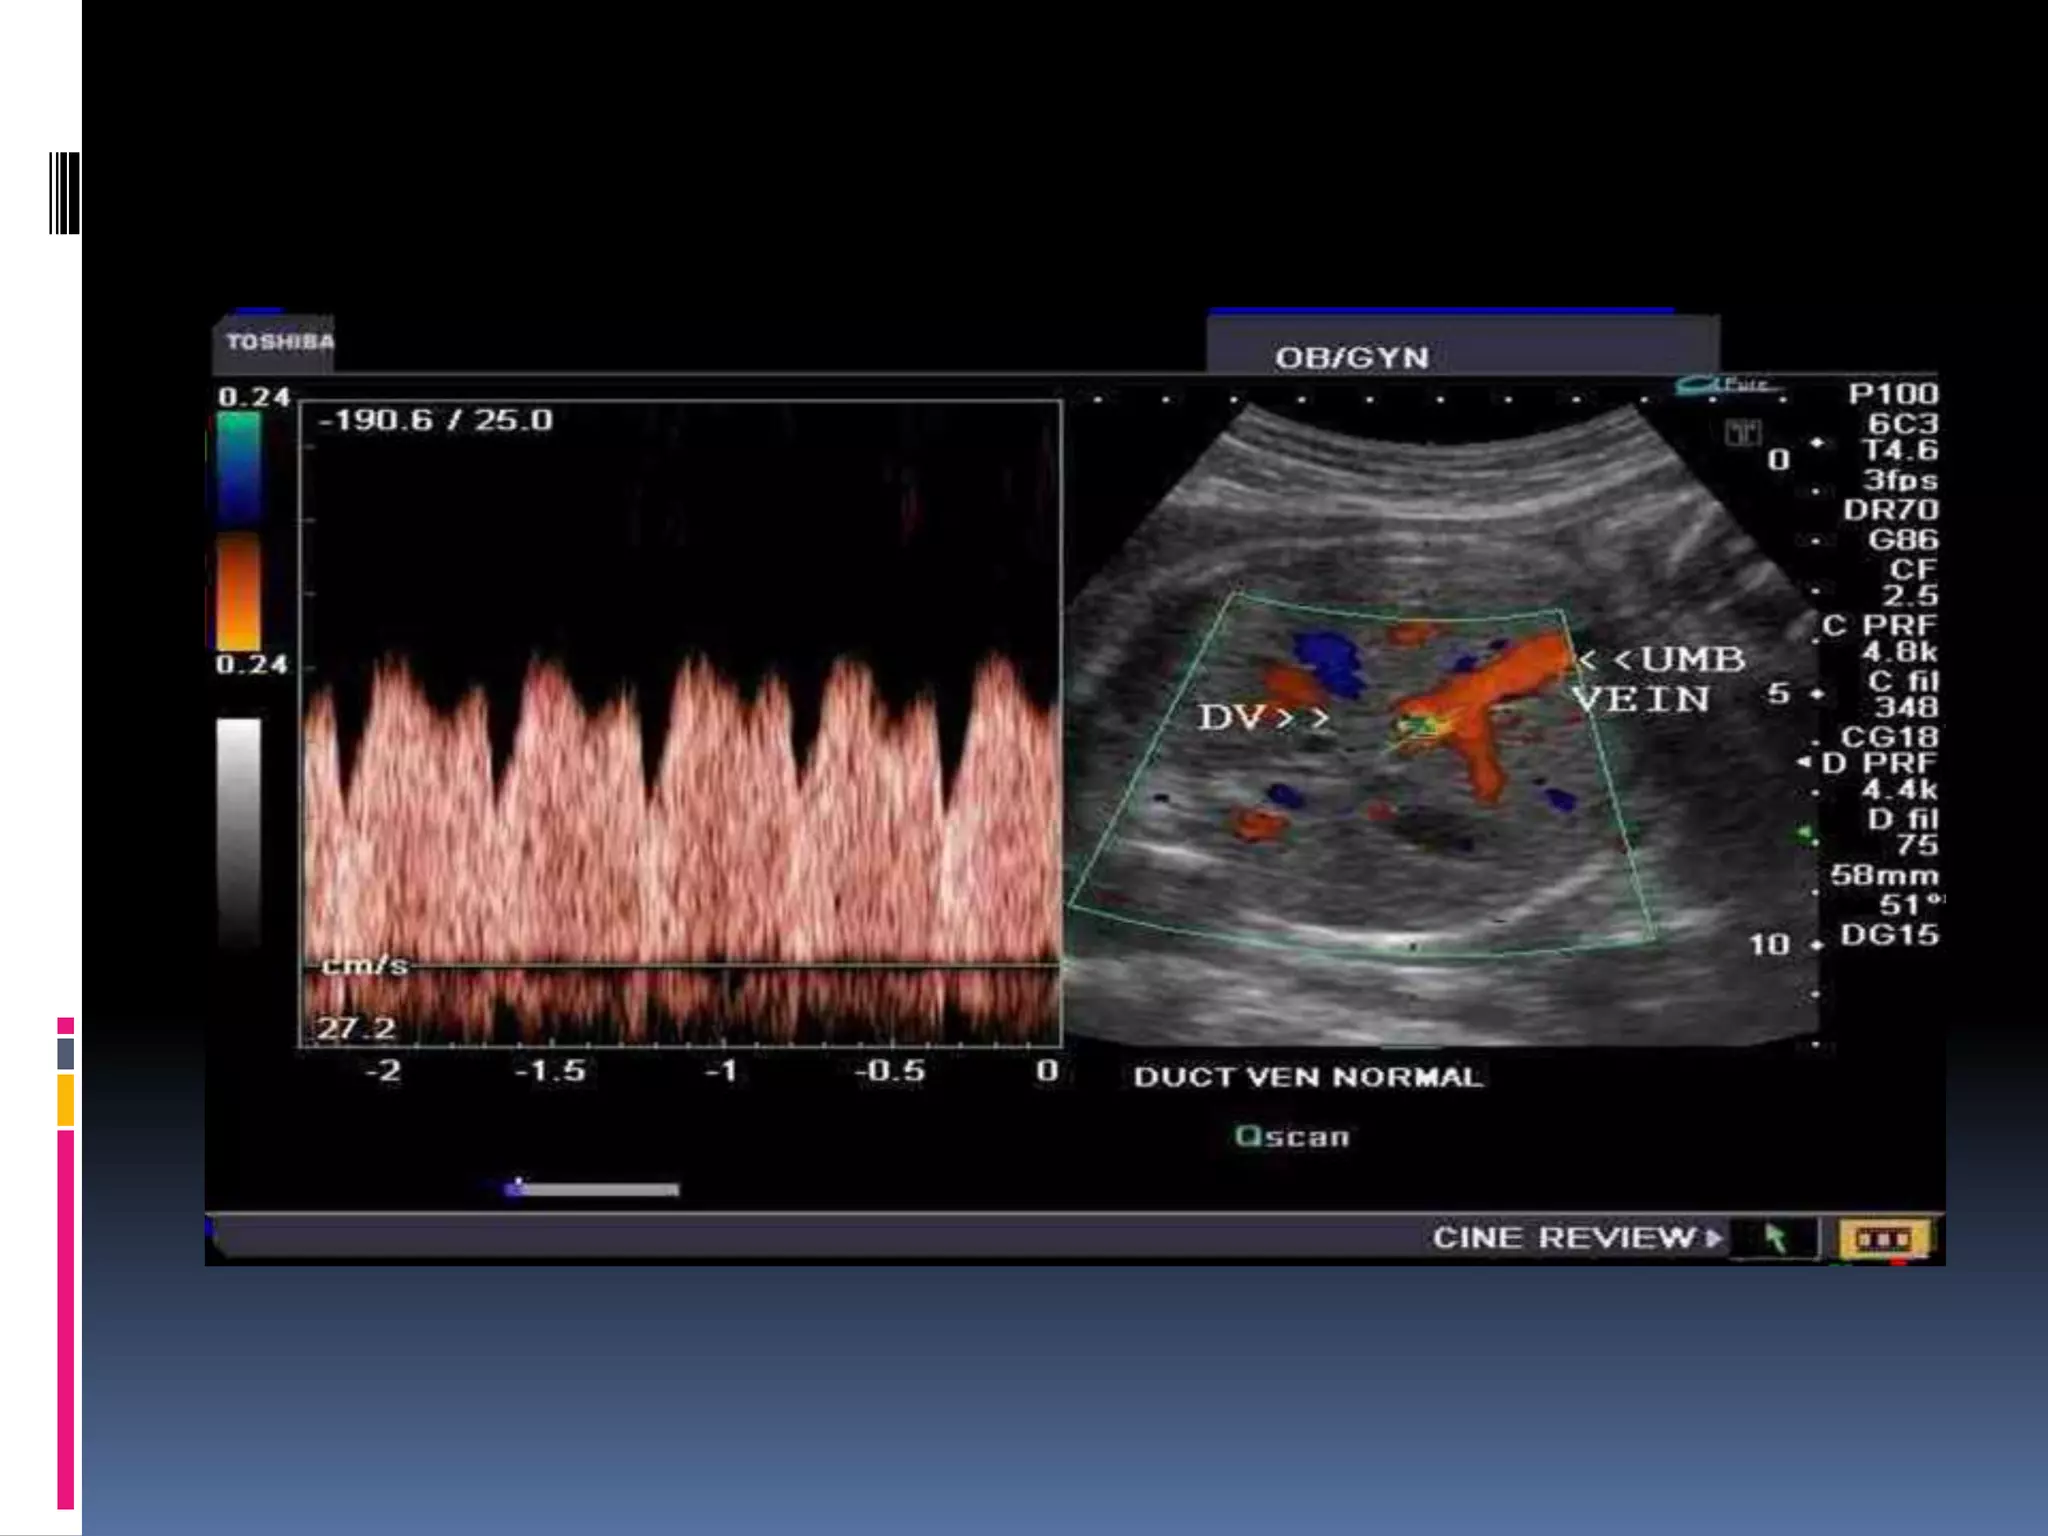

DUCTUS VENOSUS

Doppler velocity waveforms of the ductus venosus

in a normal fetus in the third trimester of

pregnancy.